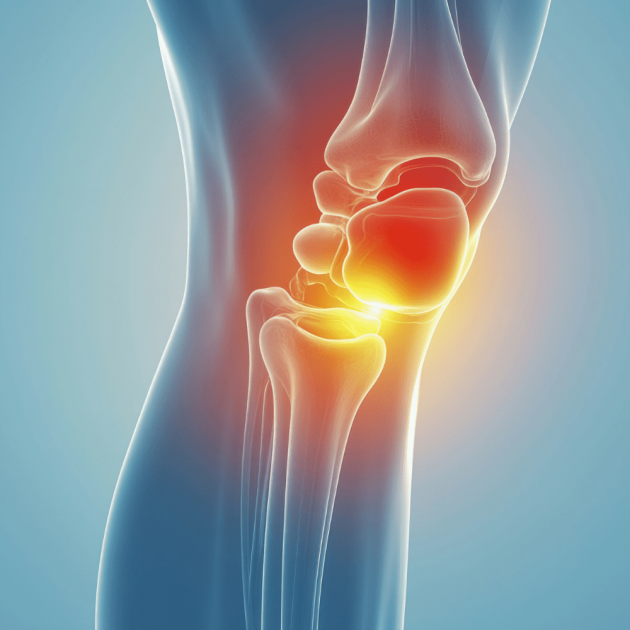

Lower Body